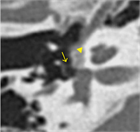

1. 前庭窓前縁の海綿状骨増殖によりアブミ骨固着が生じ、後天性・進行性伝音難聴を来す疾患である。両側罹患が多いが片側例もある。

1. 迷路骨包全体に脱灰病巣が拡大すると、蝸牛障害が加わって混合難聴、まれに高度難聴(中途失聴)に至る例もある。